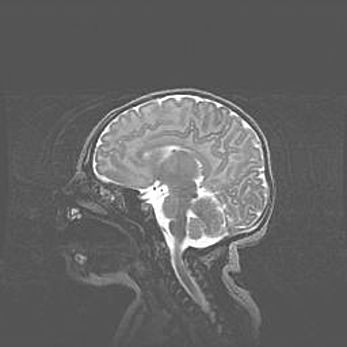

Открытая гидроцефалия.

Возраст: 9 месяцев 12 дней

Вес: 6800 г

Пол: мужской

Окружность головы: 41,5 см

Срок гестации: 28 недель

Гидроцефалия головного мозга у новорожденных имеет характерный признак: опережающий рост окружности головы приводит к визуально хорошо определяемой гидроцефальной форме сильно увеличенного в объёме черепа. Детские неврологи определяют следующие симптомы гидроцефалии у грудничков: выбухающий напряжённый родничок, частое запрокидывание головы, смещение глазных яблок к низу.